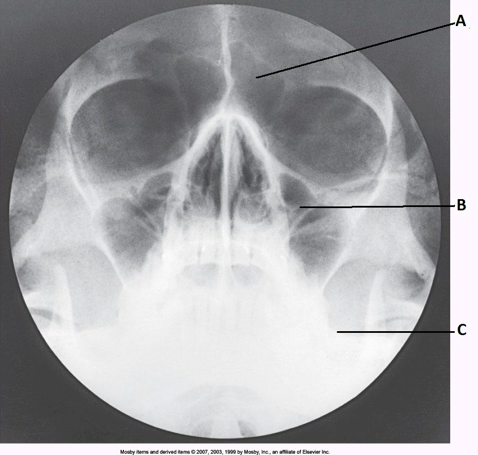

__ 7. Examine the image of the paranasal sinuses below. The letter B labels the:

a. ethmoid sinuses

b. sphenoid sinuses

c. maxillary sinuses

d. frontal sinuses

____ 13. Examine the image of the paranasal sinuses below. The letter A labels the:

a. sphenoid sinuses

b. frontal sinuses

c. ethmoid sinuses

d. maxillary sinuses

bb. frontal sinuses

____ 32. Examine the image of the paranasal sinuses below. The letter A labels the:

c. crista galli

d. ethmoid sinuses

____ 61. Examine the image of the paranasal sinuses below. The letter C labels the:

a. petrous ridge

b. vomer

c. sphenoid sinuses

d. condyle of the mandible

aa. petrous ridge